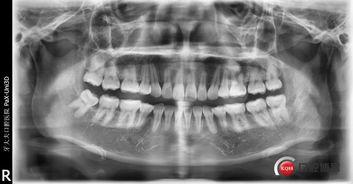

首先,得先弄清楚什么是硬腭拔牙。硬腭,就是上颚骨,拔牙嘛,就是医生把牙齿从牙槽骨里拔出来。对于成人来说,硬腭拔牙可能是因为牙齿长得不整齐,或者是因为牙齿损坏严重,需要拔除。